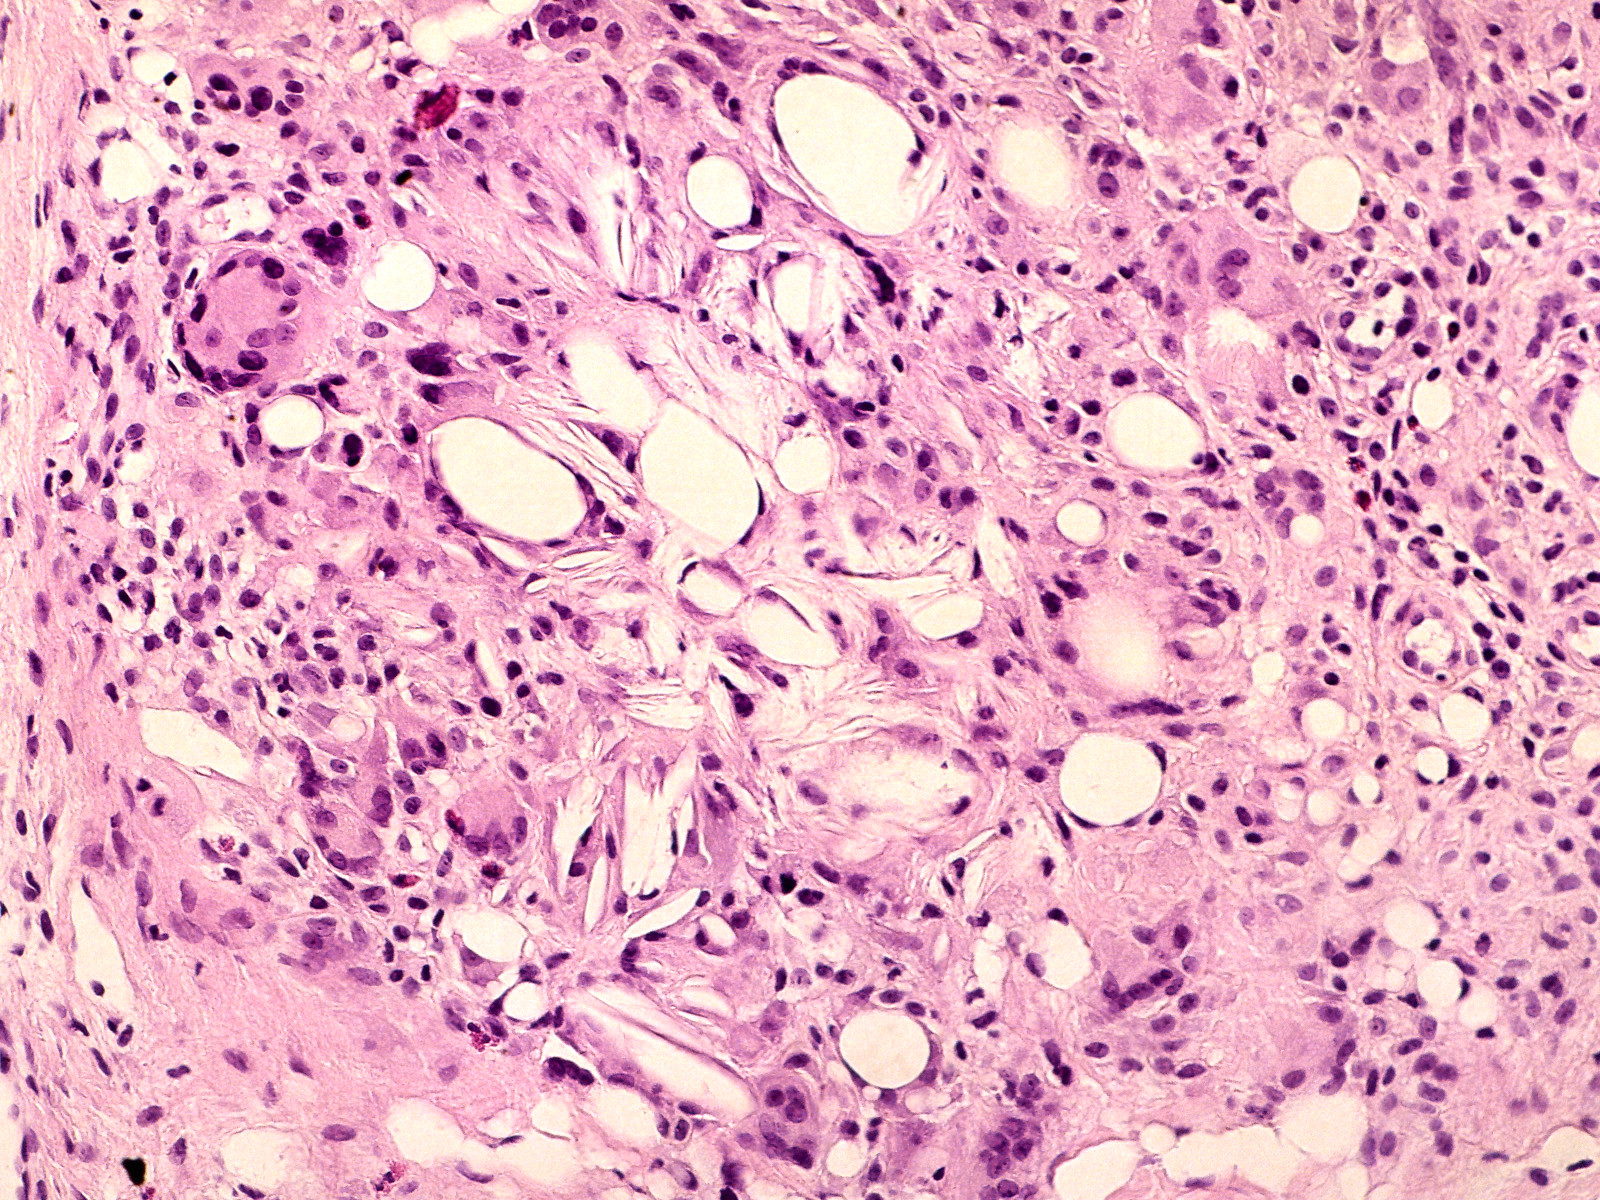

Diagnostiek:De diagnose wordt gesteld

op klinisch beeld en een diep biopt. Een punctie met een naald kan ook de diagnose

opleveren. Histologisch ziet men uitgebreide vetnecrose, vet kristallisatie,

calciumdeposities en rond de haarden van vetnecrose een uitgebreid granulomateus

ontstekingsinfiltraat van lymfocyten, macrofagen en reuscellen.